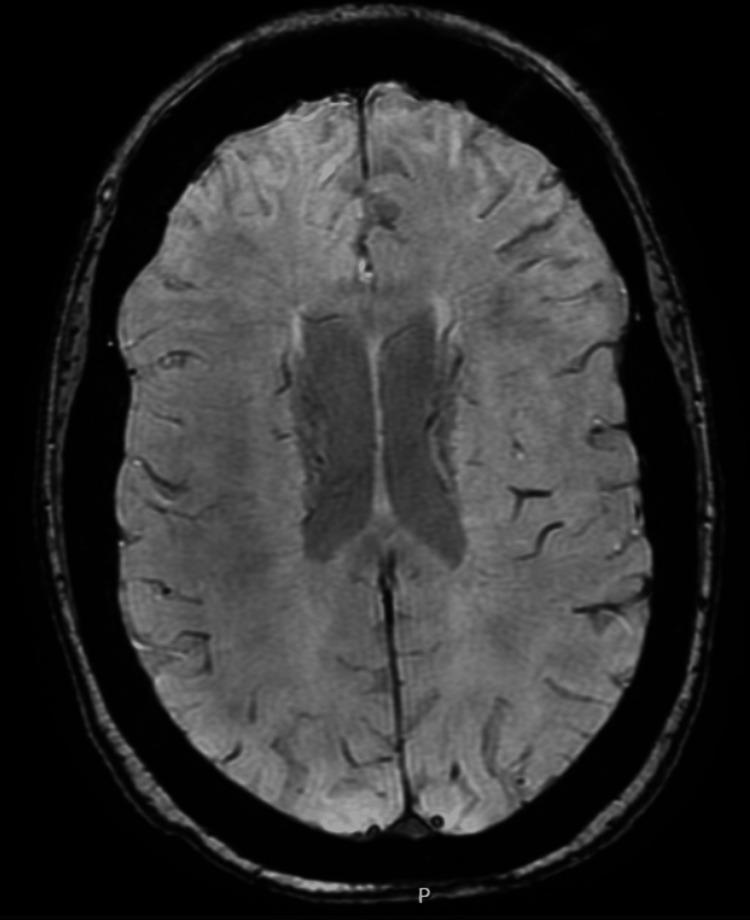

We report a rare case of late-onset hypocalcaemia presenting with seizure in a female patient, occurring approximately 25 years after a total thyroidectomy. Initial investigations ruled out intracranial pathology, and biochemical analysis confirmed severe hypocalcaemia. The patient responded to intravenous calcium gluconate infusion, with subsequent stabilisation on oral calcium therapy. Notably, the patient had been non-compliant with long-term calcium supplementation. This report underscores that chronic hypocalcaemia can manifest with acute neurological symptoms such as seizures and highlights the importance of long-term follow-up for post-thyroidectomy patients.

我们报告了一例罕见的迟发性低钙血症病例,该病例发生在一名女性患者身上,表现为癫痫发作,发生在全甲状腺切除术后约25年。初步检查排除了颅内病变,生化分析证实存在严重低钙血症。患者对静脉输注葡萄糖酸钙有反应,随后通过口服钙剂治疗病情稳定。值得注意的是,该患者一直未遵医嘱长期补充钙剂。本报告强调慢性低钙血症可表现为癫痫发作等急性神经症状,并突出了甲状腺切除术后患者长期随访的重要性。